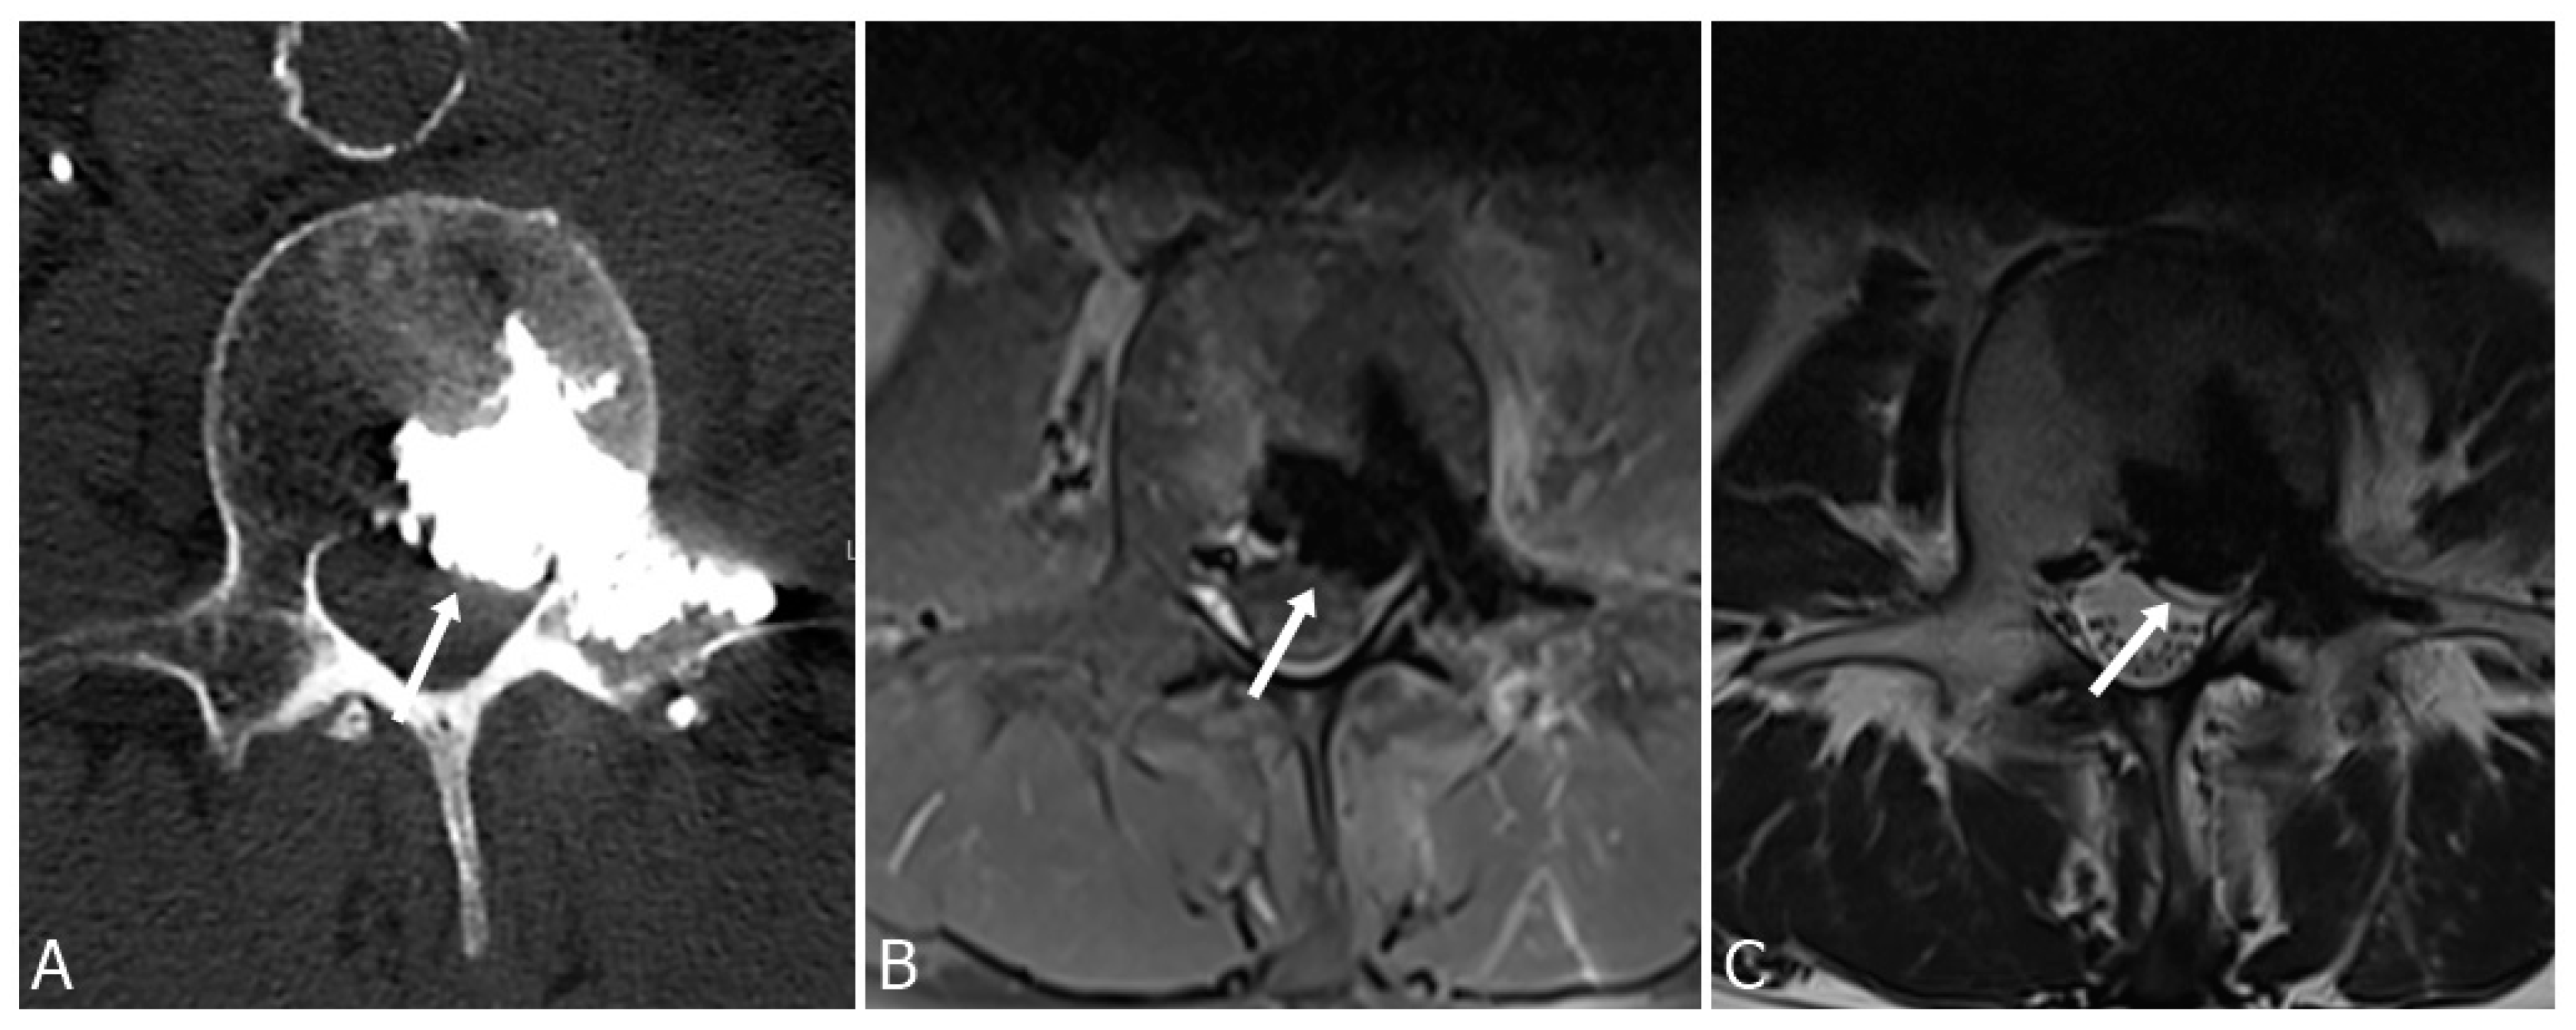

3.3. Paravertebral Soft Tissue Leakage